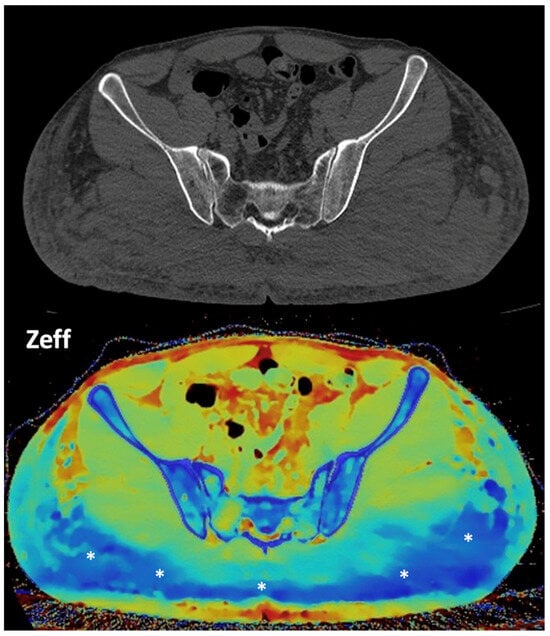

Figure 14. Lymph node (LN) imaging. Color-coded iodine maps of a left (L) axillary malignant LN (yellow arrow and yellow spectral curve, 1), which shows increased iodine uptake compared to a contralateral right (R) benign LN (blue arrow and blue spectral curve, 2). - Imaging of body composition is another growing application of DECT imaging that can be used to improve the evaluation of muscle tissue, visceral adipose tissue (VAT), and subcutaneous adipose tissue (SAT) compartments. SAT and VAT assessment is of special interest in diseases related to metabolic syndrome and critically ill patients [46]. Moreover, sarcopenia is associated with a poorer prognosis in cancer patients [47]. Measuring fat fraction of the skeletal muscle by DECT is a new approach for the determination of muscle quality, an important parameter for the diagnostic confirmation of sarcopenia [48]. In the case of bone mineral density analysis, DECT can provide a more detailed analysis when compared with dual X-ray absorptiometry [49] (Figure 15). Finally, DECT can also be a useful tool for evaluating silicone implants (Figure 16). Silicone contains the heavier element silicon (Z value = 14), whereas soft tissue predominantly comprises lighter elements, depicting the presence of silicone within the soft tissues in cases of silicone gel breast implant rupture and LN silicone spread [50].

Figure 16. Gluteal silicone injection. Unenhanced CT image (top) shows a diffuse increase in density in both gluteal areas. Silicone deposition is better evaluated in a Zeff map (bottom), which separates silicone (blue areas, asterisks) from edema based on their different atomic numbers (silicon Z = 14).